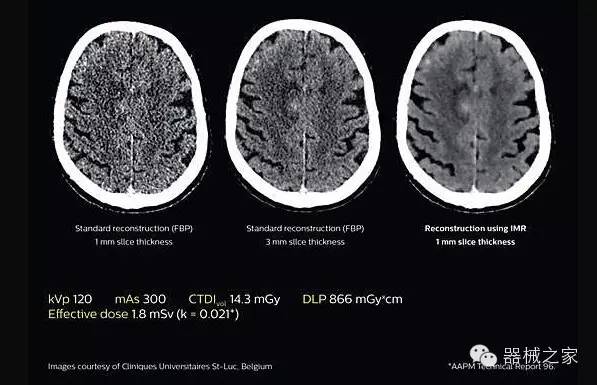

透過(guò)數(shù)字化影真芯片DAS系統(tǒng)、球面微平板探測(cè)器技術(shù)和濾線柵技術(shù)等硬件技術(shù),整體提高探測(cè)器成像的能力,奠定低劑量條件下高清成像的基礎(chǔ);

應(yīng)用目前業(yè)界領(lǐng)先的新一代星光平臺(tái)iDose4 Premium及基于迭代基礎(chǔ)的O一MAR去除金屬偽影技術(shù),達(dá)成微量輻射下零偽影的高清晰成像;

2.腦部顯影